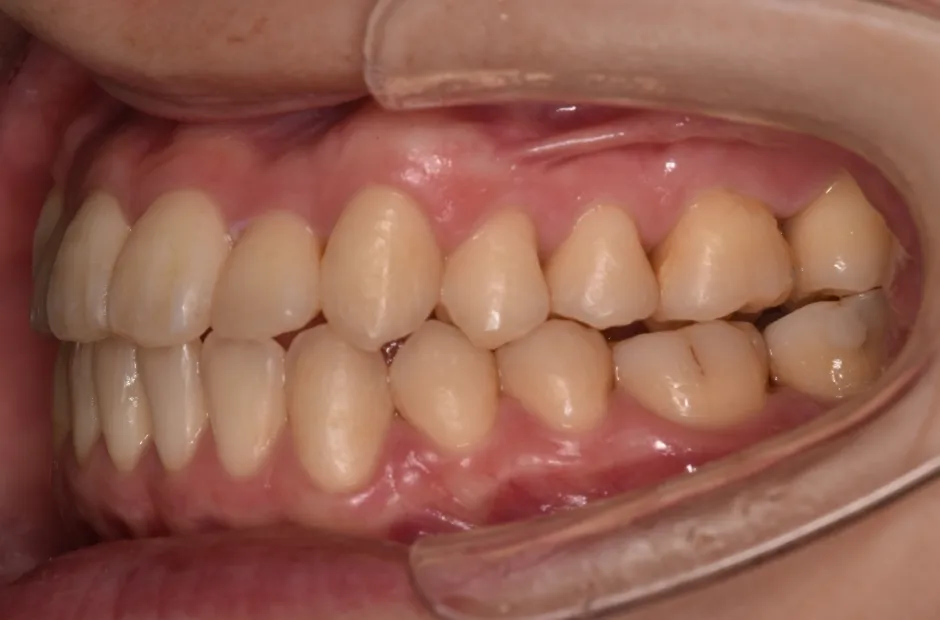

叢生

| 診断名・主訴 | 叢生 |

|---|---|

| 年齢・性別 | 43歳・女性 |

| 治療期間・回数 | 2年7か月 27回 |

| 治療に用いた主な装置 | 舌側矯正 |

| 抜歯部位 | 両顎4,4 |

| 治療費 | 100万円(税抜) |

| リスク・副作用 | 装置による違和感・疼痛・歯肉退縮・歯根吸収・虫歯のリスクなど |

治療後